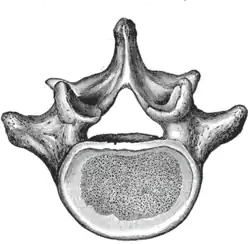

The adjacent figure depicts the general characteristics of the first through fourth lumbar vertebrae. The fifth vertebra contains certain peculiarities, which are detailed below.

As with other vertebrae, each lumbar vertebra consists of a vertebral body and a vertebral arch. The vertebral arch, consisting of a pair of pedicles and a pair of laminae, encloses the vertebral foramen (opening) and supports seven processes.

Body

The vertebral body of each lumbar vertebra is kidney shaped, wider from side to side than from front to back, and a little thicker in front than in back. It is flattened or slightly concave above and below, concave behind, and deeply constricted in front and at the sides.[1]

Arch

The pedicles are very strong, directed backward from the upper part of the vertebral body; consequently, the inferior vertebral notches are of considerable depth.[1] The pedicles change in morphology from the upper lumbar to the lower lumbar. They increase in sagittal width from 9 mm to up to 18 mm at L5. They increase in angulation in the axial plane from 10 degrees to 20 degrees by L5. The pedicle is sometimes used as a portal of entrance into the vertebral body for fixation with pedicle screws or for placement of bone cement as with kyphoplasty or vertebroplasty.

The laminae are broad, short, and strong.[1] They form the posterior portion of the vertebral arch. In the upper lumbar region the lamina are taller than wide, but in the lower lumbar vertebra the lamina are wider than tall. The lamina connects the spinous process to the pedicles.

The vertebral foramen within the arch is triangular, larger than the thoracic vertebrae, but smaller than in the cervical vertebrae.[1]

Processes

The spinous process is thick, broad, and somewhat quadrilateral; it projects backward and ends in a rough, uneven border, thickest below where it is occasionally notched.[1]

The superior and inferior articular processes are well-defined, projecting respectively upward and downward from the junctions of pedicles and laminae. The facets on the superior processes are concave, and look backward and medialward; those on the inferior are convex, and are directed forward and lateralward. The former are wider apart than the latter since in the articulated column, the inferior articular processes are embraced by the superior processes of the subjacent vertebra.[1]

The transverse processes are long and slender. They are horizontal in the upper three lumbar vertebrae and incline a little upward in the lower two. In the upper three vertebrae they arise from the junctions of the pedicles and laminae, but in the lower two they are set further forward and spring from the pedicles and posterior parts of the vertebral bodies. They are situated in front of the articular processes instead of behind them as in the thoracic vertebrae, and are homologous with the ribs.[1]